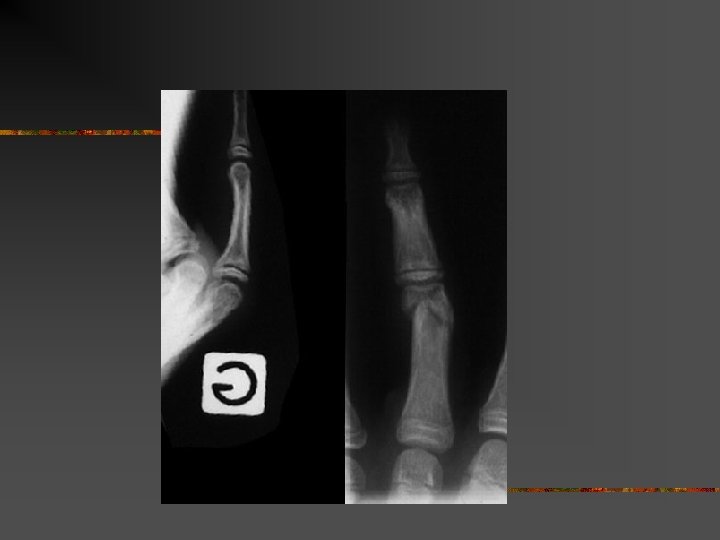

Le doigt en maillet n n Désinsertion de l’extenseur sur P 3 Arrachement osseux parfois

Le doigt en maillet

Traitement n n n Orthopédique+++ Attelle en extension pendant 6 semaines nuit et jour Puis 15 jours la nuit